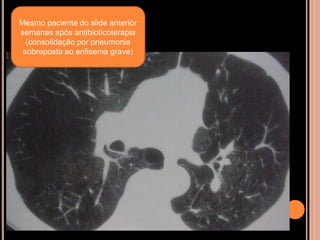

Mesmo paciente do slide anterior

semanas após antibioticoterapia

(consolidação por pneumonia

sobreposta ao enfisema grave)

Mesmo paciente doslide anterior semanas após antibioticoterapia (consolidação por pneumonia sobreposta ao enfisema grave)